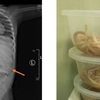

MALANG, KOMPAS.com - Kasus bocah di Jember yang harus dioperasi karena perutnya dipenuhi cacing membuat banyak orangtua tercengang.

Baca juga: Kasus Perut Anak Penuh Cacing Ascariasis, Ini 2 Penyebab Anak Tak Bisa BAB Menurut Dokter

Baca juga: Ini Gejala dan Penyebab Perut Anak Bisa Dipenuhi Cacing Ascariasis yang Perlu Diwaspadai